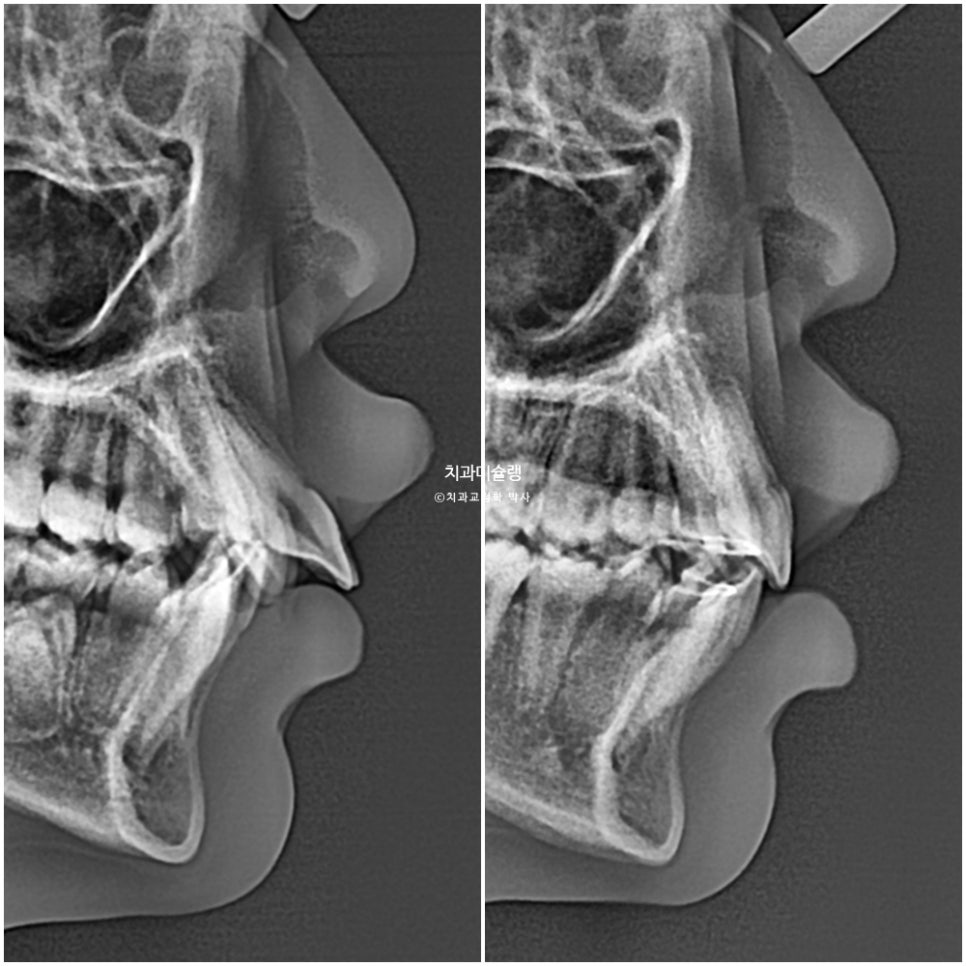

이제 전후비교 보겠습니다.

2023.07-2025.12

과개교합, 중심선의 개선.

앞니 돌출의 개선

2급 교합관계가 1급 교합관계로 개선되었습니다.

치근흡수는 없었으며 제2대구치가 잘 올라오는 중입니다.